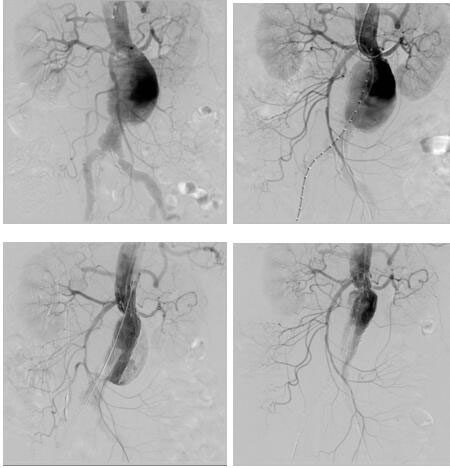

血管介入科完成我院首例腎下復(fù)雜型腹主動(dòng)脈瘤腔內(nèi)修復(fù)

日前,血管介入科為一位患腎下復(fù)雜型腹主動(dòng)脈瘤(左腎動(dòng)脈距離瘤體僅4mm)74歲老年女性完成腎動(dòng)脈煙囪+腹主動(dòng)脈瘤覆膜支架腔內(nèi)隔絕術(shù),術(shù)后恢復(fù)良好。該患者基礎(chǔ)疾病多,已經(jīng)出現(xiàn)腹痛癥狀,腹主動(dòng)脈瘤瘤體隨時(shí)有破裂風(fēng)險(xiǎn),但左腎動(dòng)脈距離瘤體僅4mm,采取傳統(tǒng)開(kāi)放手術(shù)(腹主動(dòng)脈瘤切除+Y型人工血管置換+左腎動(dòng)脈轉(zhuǎn)流術(shù))手術(shù)創(chuàng)傷大,手術(shù)風(fēng)險(xiǎn)高,經(jīng)血管外科治療團(tuán)隊(duì)反復(fù)研究病例,并在院領(lǐng)導(dǎo)支持下,決定采取腔內(nèi)治療:先經(jīng)肱動(dòng)脈穿刺置鞘于左腎動(dòng)脈留置導(dǎo)絲,再經(jīng)雙側(cè)股動(dòng)脈上導(dǎo)絲導(dǎo)管造影定位,在施放腹主動(dòng)脈主體支架前先經(jīng)左肱動(dòng)脈留置導(dǎo)絲導(dǎo)引下于左腎動(dòng)脈置入VIABAHN支架保證左腎動(dòng)脈供血,再釋放腹主動(dòng)脈主體支架,解決了左腎動(dòng)脈距離瘤體過(guò)近的問(wèn)題。該例手術(shù)的完成,標(biāo)志著我院在腹主動(dòng)脈瘤的腔內(nèi)治療跨入省內(nèi)領(lǐng)先行列。